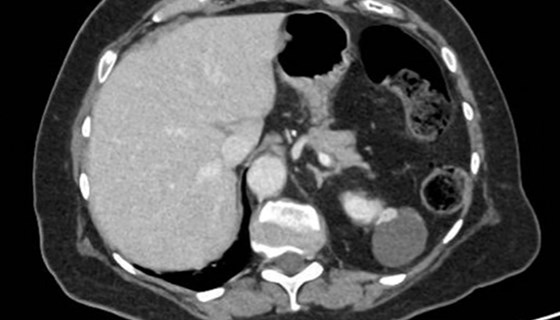

Advanced renal tumours

Case 1 A 67-year-old gentleman underwent a CT scan after presenting with visible haematuria and weight loss. His comorbidities include hypertension, type II diabetes mellitis and hypercholesterolaemia. He is a smoker. Figure 1. Figure 2. What do Figures 1 and...